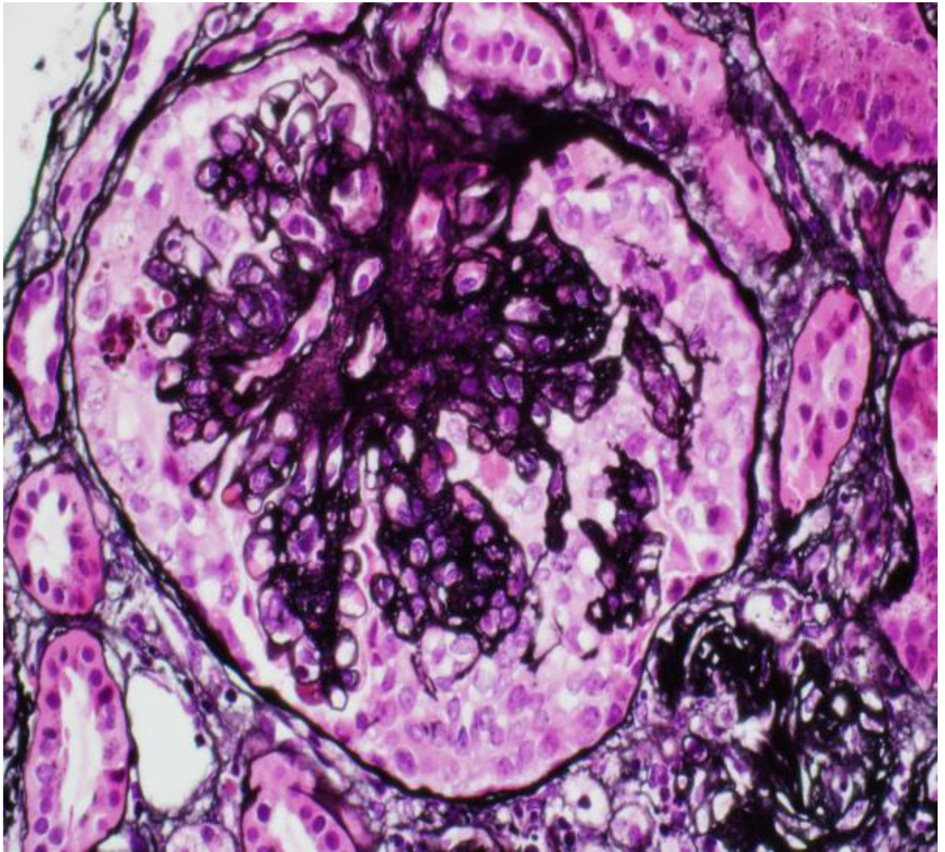

The patient is an 18-year-old male patient from south region of Saudi Arabia. He is known to have CD on gluten-free diet only based on clinical presentation and small intestinal biopsy 2 year ago. He is a short stature young man, and was not on any medication before with no family history of kidney disease/autoimmune disease. He came to our hospital with history of generalized body swelling with blood pressure 118/72 mm Hg. Lab showed blood urea nitrogen (BUN) of 9.9 mg/dL, creatine of 124 mmol/L and hemoglobin of 14.6 g/L. Additional testing revealed a low serum albumin of 10.1 g/L and proteinuria of 6 g/day; antinuclear antibody (ANA), complement 3 (C3) and complement 4 (C4) were normal. Hepatitis B, C serology and HIV screen were also negative. Renal biopsy was done and showed renal cortex with 12 glomeruli present for evaluation. None revealed global sclerosis and three showed lesion of segmental sclerosis with collapsing features. The remaining glomeruli showed normal architecture with normal thickness of capillary walls and patent capillary lumina. There is mild multifocal interstitial fibrosis and tubular atrophy (15-20% of cortical tissue), associated with minimal focal interstitial lymphocyte infiltration. Vascular compartment is within normal limits and on electron microscopy (EM13-679), the semithin section revealed one glomerulus (Fig. 1). Ultrastructure examination demonstrated peripheral capillary walls with normal thickness, contours and texture, mesangial areas are unremarkable, and no electron dense deposits are seen. The podocytes showed diffuse foot process effacement. Patient was started on lisinopril 5 mg to control the proteinuria and furosemide 40 mg BID for the edema, along with atorvastatin 20 mg oral daily. Prednisone 60 mg/day was used, after 2 months follow-up, symptoms and laboratory results started to improve.

![]() Click for large image | Figure 1. Renal biopsy. |